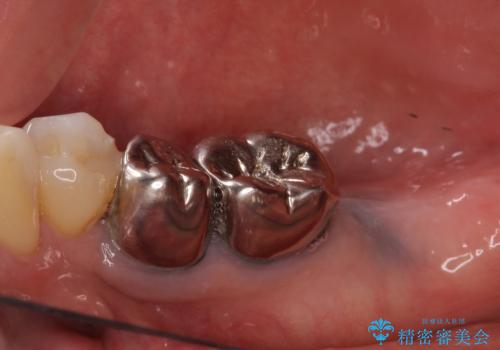

- 奥歯の欠損部へのインプラント治療を希望して来院された患者様です。

抜歯をしてから長年経過しており、レントゲンからは十分に骨があることが分かっていたため、速やかに治療を開始することとしました。

インプラント治療に当たり、手前の銀歯2本の審美回復も希望されたため、3歯のオールセラミッククラウンによる補綴治療を行うこととしました。